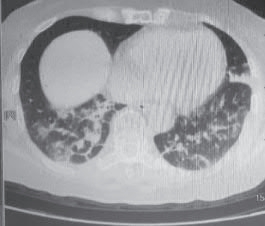

(4)胸部影像变化。

2022-12-25 胸部CT(图2-6-4):双肺散在多发感染性病变,较前有所吸收、减少。

图2-6-4 2022-12-25 胸部CT